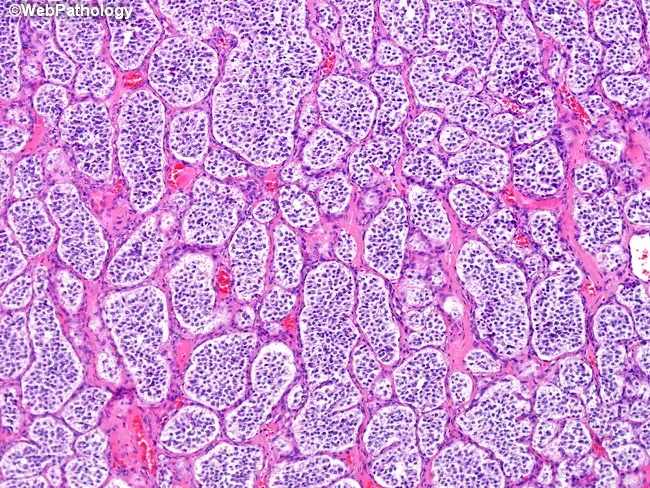

Pheochromocytoma - Adrenaline Rush Hour

- Neuroendocrine tumor of chromaffin cells (adrenal medulla; or extra-adrenal paraganglia e.g., organ of Zuckerkandl). Secretes catecholamines (mainly Norepinephrine, Epinephrine).

- Diagnosis: ↑ urine VMA/HVA; biopsy shows small, round, blue cells, Homer-Wright pseudorosettes.

- Neuroblastoma: Homer-Wright pseudorosettes on histology; N-myc amplification signifies poor prognosis.